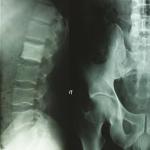

Cystite emphysémateuse

Une patiente de 89 ans, sans antécédent majeur, consulte aux urgences à la suite d’une chute accidentelle avec fracture...